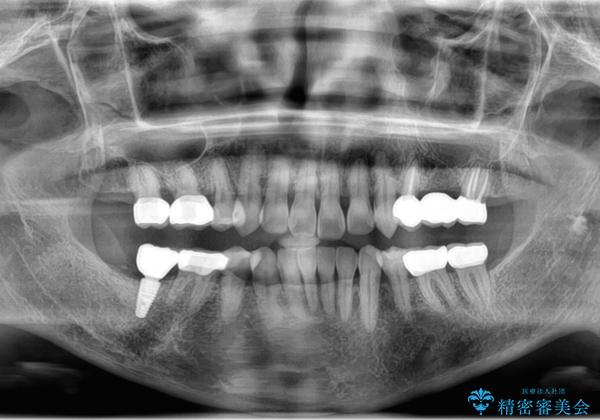

- ぐらぐらする歯や銀歯、なんとなくにおいのする奥歯の治療を求めて来院されました。

X線、歯周組織検査の結果、全体的に奥歯には重度〜中等度の歯周病の問題が見られました。

残すことのできない歯、予後の悪い歯を抜去し、ブリッジイ・ンプラントによる機能回復をおこなっていくと同時に、残すことのできる歯には歯周病治療をしっかりと行い、

将来に渡りしっかりと自分の歯で噛めるような口腔内環境を構築していきます。